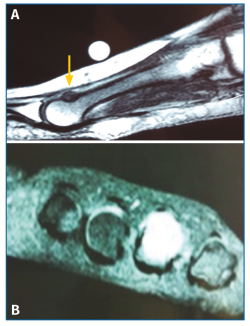

El estudio radiográfico en carga no mostraba alteraciones en la fórmula metatarsal ni lesiones óseas (Figura 1).

Figura 1. Radiología simple anteroposterior en carga (A) y oblicua antepié (B) sin lesiones óseas a nivel del 4.º metatarsiano.